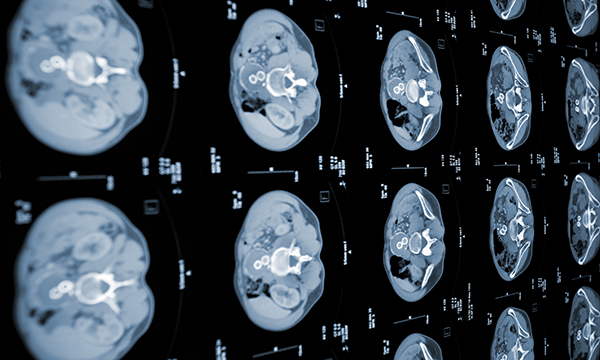

Artificial intelligence (AI) has great potential to transform cancer diagnosis and treatment, so nurses should look for opportunities to learn more about it

This is a summary of the peer-reviewed article: Abdominal X-rays in children: indications, proced